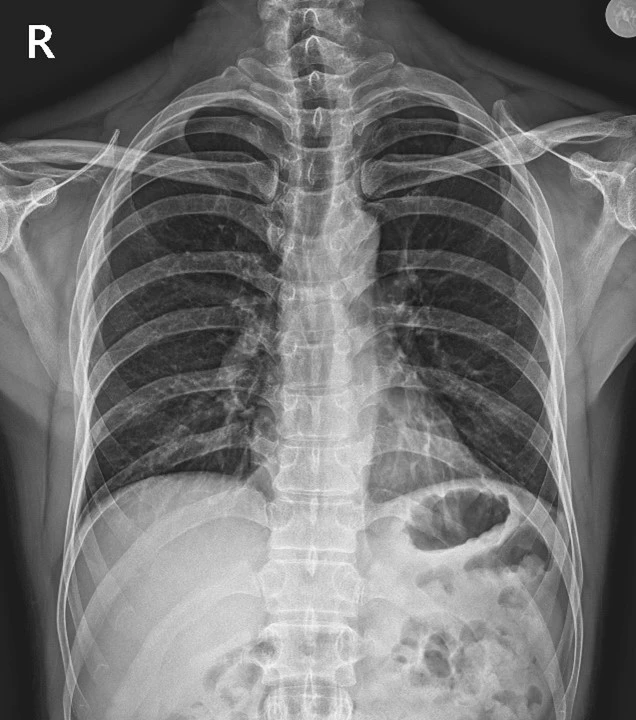

환자분이 가져오신 MRI를 꼼꼼히 살펴봤습니다.

그리고 X-ray도 다시 촬영했어요.

%EA%B7%B8%EB%A6%BC3.jpg?type=w966

<Fig 1. 이상 소견 없는 MRI>

솔직히 말씀드리면, 늑간신경통은 진단이 쉽지 않습니다.

MRI에서도 명확히 보이지 않는 경우가 많고,

증상만으로는 목디스크나 어깨 질환과 구분이 모호할 수 있거든요.